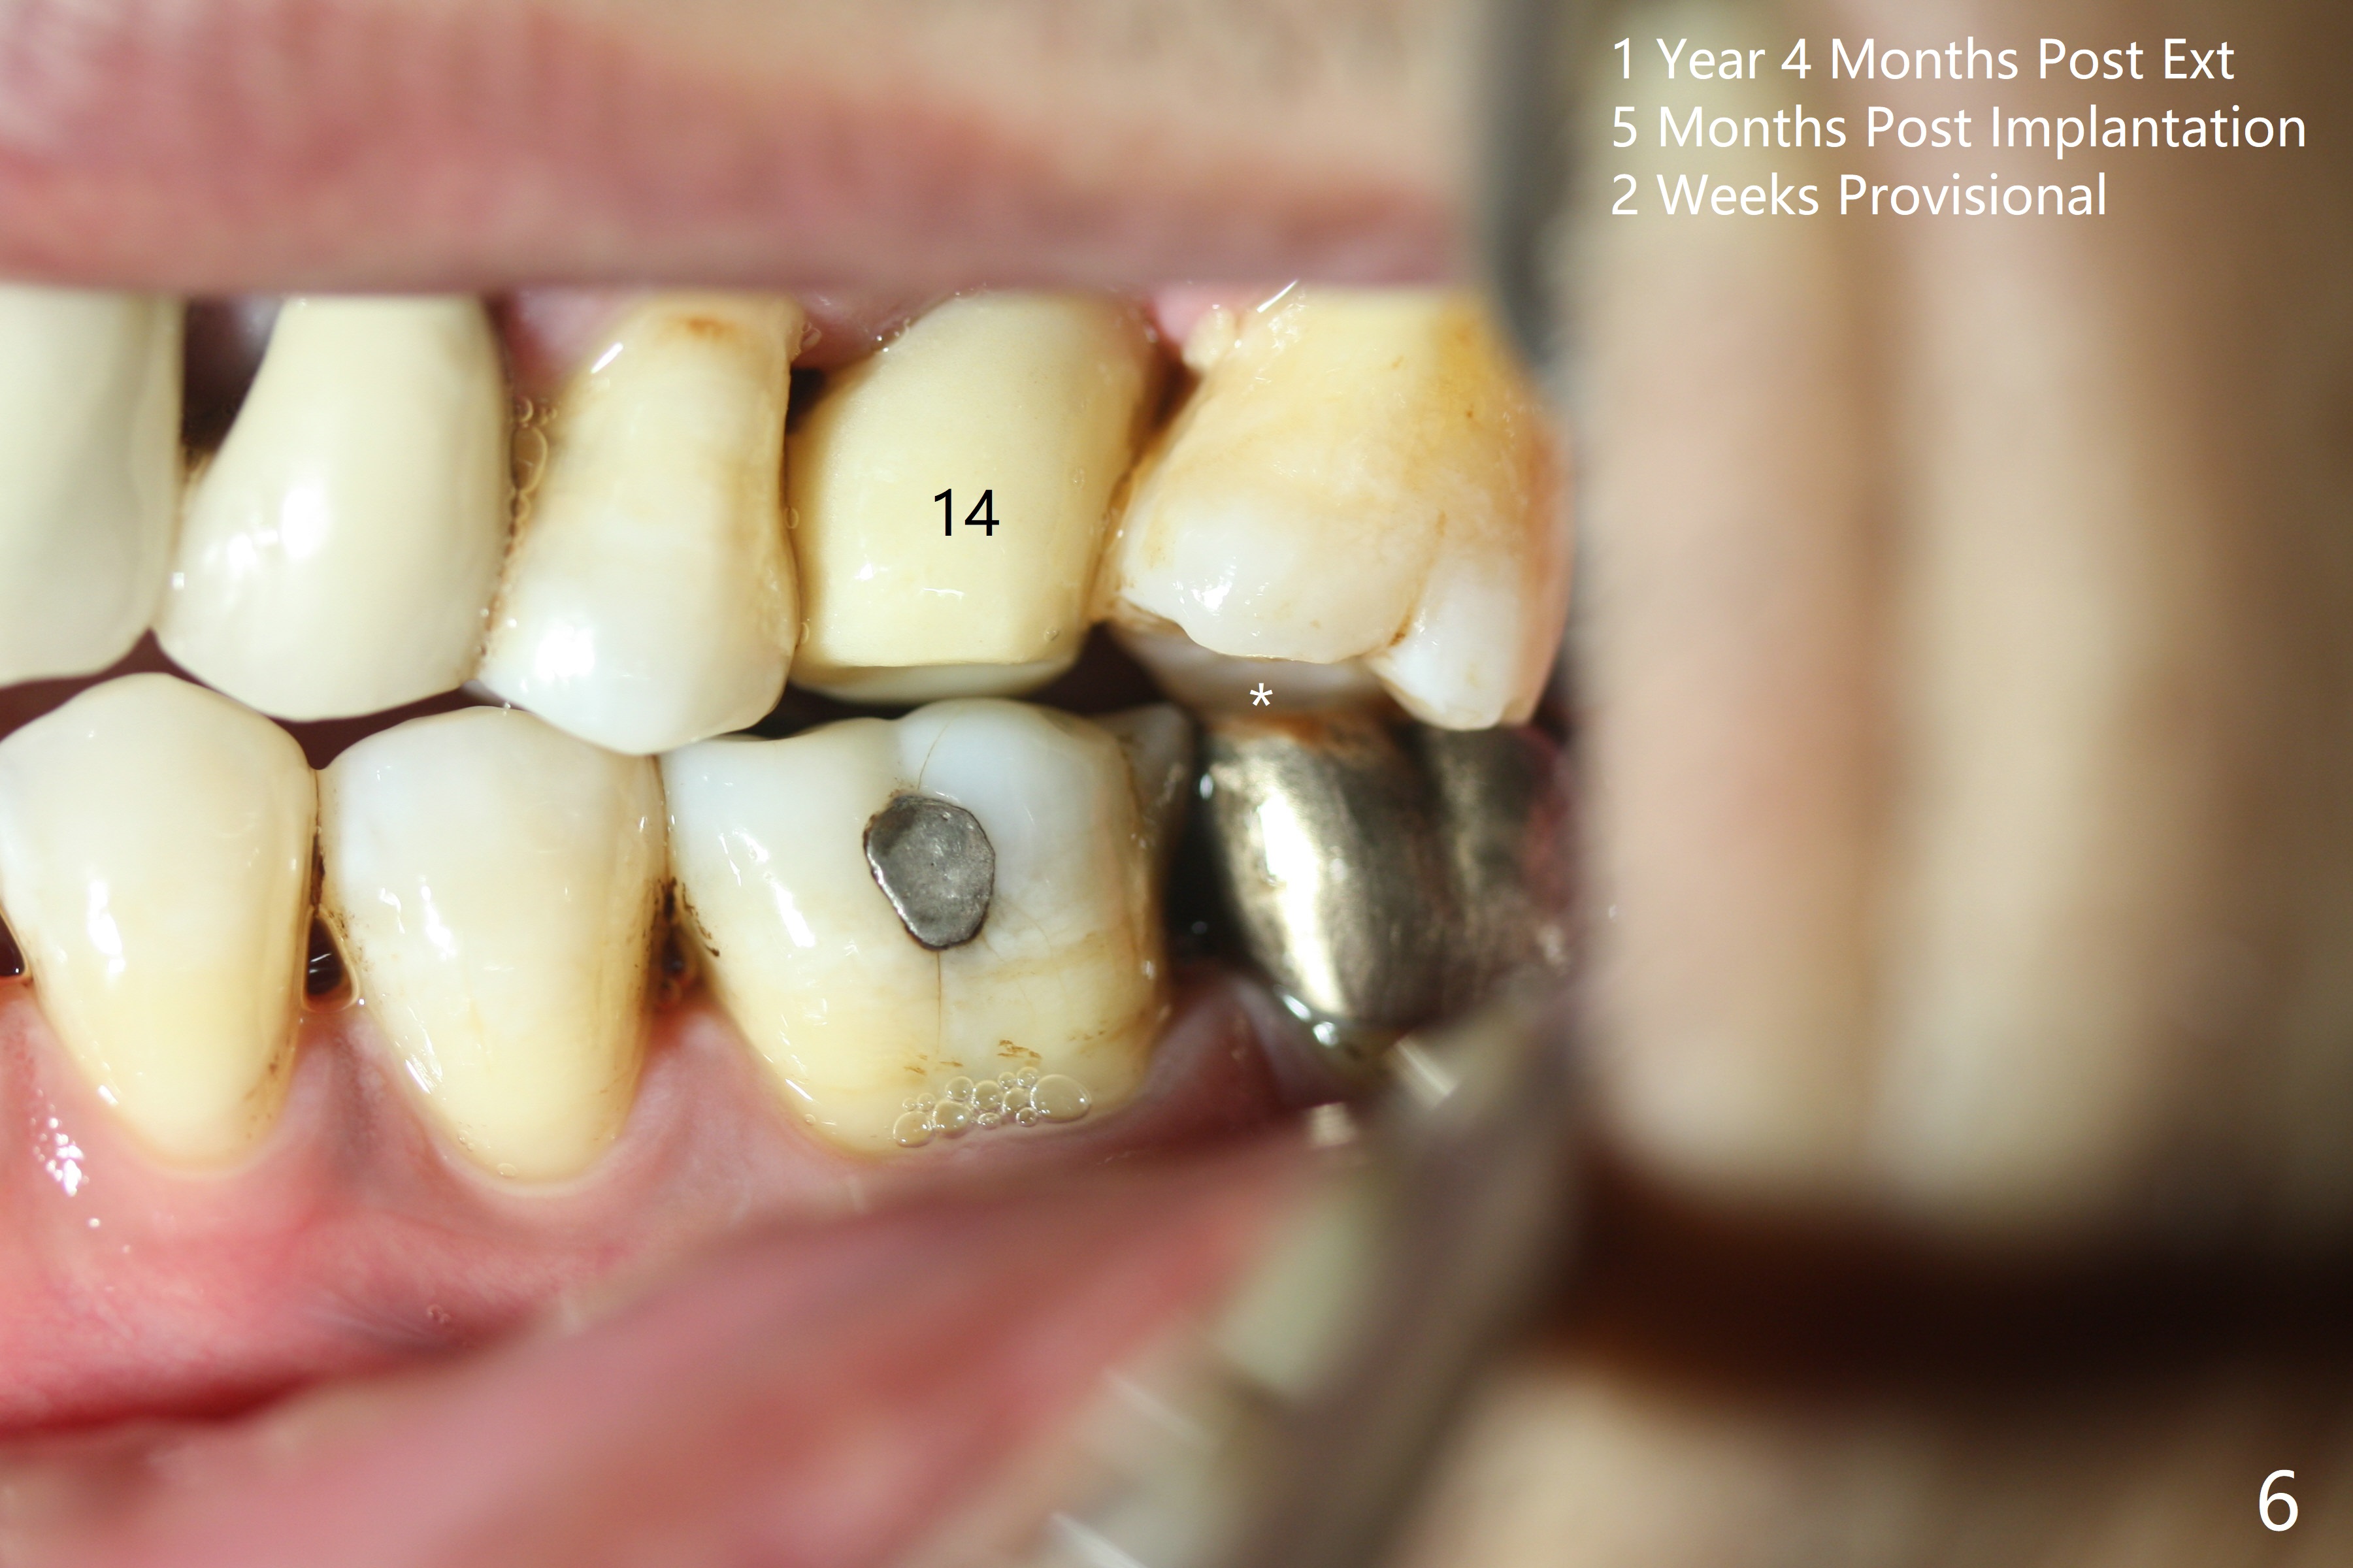

Six months post 2nd placement at #14, the 5x11 mm IBS implant is unstable. The patient smokes a cigarette a day.  After implant removal, the palatal wall of the osteotomy is intact, although low.  With removal of minimal granulation tissue, a 5x10 mm IS dummy implant is placed with stability and slightly subgingival palatal (Fig.1,2).  A 5x8.5 mm definitive implant is placed with ~ 40 Ncm and 3-4 mm subgingival palatal (Fig.3,4).  A 5.7x5.5(5) mm abutment is placed to hold periodontal dressing in place.  If the implant fails again, bone graft should be placed.  The abutment and implant are stable 4.5 months postop (Fig.5); a provisional is fabricated for progressive loading.  The provisional at #14 is narrow mesiodistally, while the tooth #15 is mesially tilted and shifted because of chronic periodontitis and 1 year 4 months of edentulism (Fig.6*).  Limited orthodontics is necessary prior to final restoration.  The 1st step is to raise the occlusion with #14 temporary reline (Fig.7 *); the tooth #15 is distalized initially with a separator, which is inefficient.  It appears that brackets and bands should be placed for distalization.  A month post banding, open coil spring is placed between #14 and 15; with occlusal composite on the opposing tooth (#19) (Fig.8), the tooth #15 is distalized instantly probably related to its periodontal condition (Fig.9 mirror view).  The tooth #15 is further distalized 2 weeks post open coil spring placement (Fig.10).  To act an anchorage, the abutment needs to be torqued with wrench (25-30 Ncm) and the provisional has to be permanently cemented.  The distalization appears to be ~ 1 mm shy 1.5 months post open coil (Fig.11).